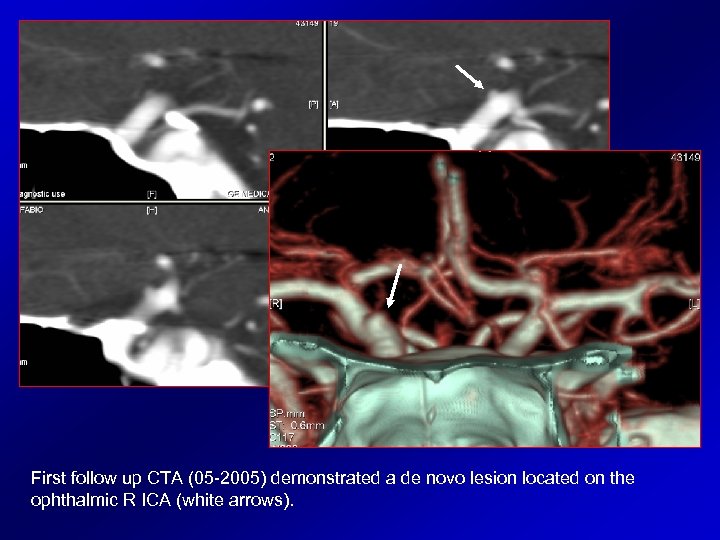

Pt 10 male 25 y. o. Pre-treatment DSA 07 -1998 Post-treatment angiograms 03 -1999: note the regular profile of the cavernous and ophthalmic R ICA and absence of lesions in the L MCA trifurcation

First follow up CTA (05 -2005) demonstrated a de novo lesion located on the ophthalmic R ICA (white arrows).